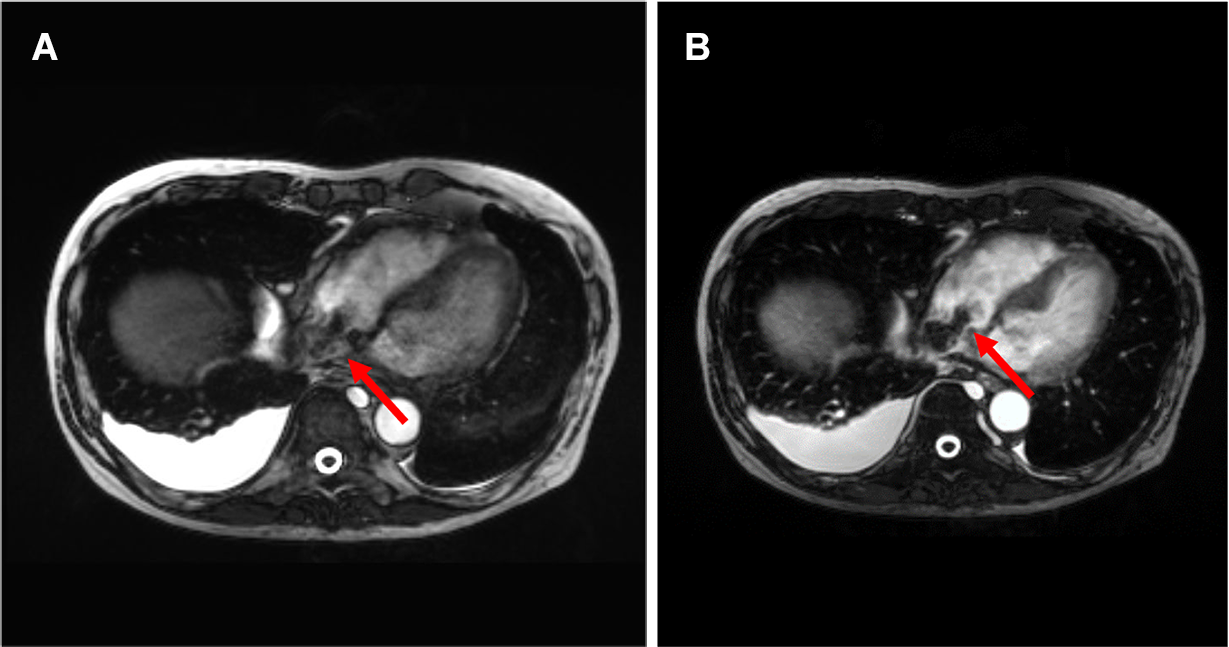

図2.ガドビスト造影MRI (A:T2WI B:DWI(b=800) C:ADCmap D:造影前脂肪抑制T1WI E:造影後脂肪抑制T1WI F:造影後True FISP G:造影後TrueFISP冠状断像)

(A-F→)下大静脈内の腫瘍はT2WI低信号で、DWIで不均一な高信号、ADCは軽度低下している。hypovascularであり、造影True FISP冠状断像で頭側は右房内(➤)、尾側は右腎静脈起始部(⇒)、左腎静脈(➔)に及んでいることがわかる。

転移性肝腫瘍の経過観察でプリモビストMRIを行っており、心臓超音波後、hypovascularな下大静脈内腫瘍がプリモビストMRIでも確認された。腫瘍進展範囲の精査としてガドビストMRIを施行。Slow infusion造影(6倍希釈した造影剤を6分間流し続ける)のTrue FISPを加え、腫瘍周囲の血管を乱流の影響を抑え、常に高信号に描出することでhypovascularな腫瘍の正確な進展範囲が評価可能であった。